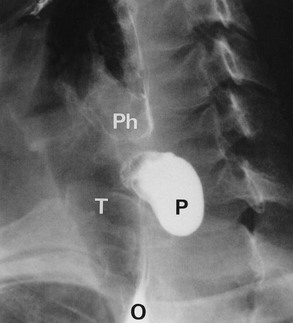

Clinically, the cardiac sphincter becomes constricted and the proximal oesophagus dilates with accumulated fluid and solids. Difficulty in swallowing is the usual presenting symptom, together with halitosis, weight loss, reflux of food into the back of the throat. Solids tend to sink to the lower end of the dilated oesophagus, whereas fluids spill over into the trachea causing spluttering dysphagia (see Ch. 18, p. 249) and coughing, particularly at night. Vomiting and retrosternal pain may occur in more severe cases.

Chest X-ray may show the mediastinal shadow is widened by a dilated oesophagus; sometimes a fluid level in the oesophagus is visible behind the heart Fig. 22.7(b). At endoscopy the typical appearance is of a capacious distal oesophagus, usually with food and fluid residue, and a tight lower oesophageal sphincter that may or may not admit the tip of the gastroscope. It is important to see the oesophago-gastric junction to exclude an occult neoplasm masquerading as achalasia (pseudoachalasia). Barium swallow examination reveals gross dilatation of the oesophagus with a tapering constriction (often described as a ‘bird’s beak’ or ‘rat’s tail’) at the lower end. The constriction barely allows contrast to enter the stomach (see Fig. 22.8). Under fluoroscopic screening, uncoordinated purposeless peristaltic waves can often be seen; these are described as tertiary contractions, distinct from normal coordinated primary and secondary contractions. Oesophageal manometry is the cardinal test for achalasia, demonstrating excessive lower oesophageal sphincter pressure that fails to relax on swallowing, and abnormal peristalsis in patients with a more chronic history.